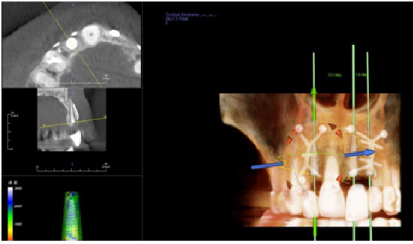

Four months later a new CBCT of the maxillary arch was completed and at all sites, #s 7. 9, and 10 with successful GBR achieved and implant placement was planned using the Anatomage (San Jose, CA, USA) implant planning software (Figures 17, Figure 18, and Figure 19). Each site went from less than 2 mm of width preoperatively to a width of 7 mm four month after grafting.

Figure 19:Post-op four months grafting #10 site CBCT and Anatomage implant planned. Notice the increased bone width from a preoperative width of less than 2 mm to a width after 4 months of 7 mm. View Figure 19